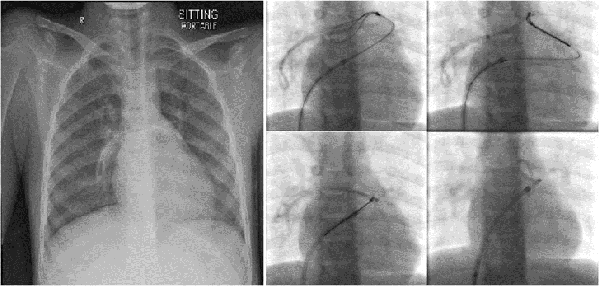

Fluoroscopy

Fluoroscopy is a low dose, real-time X-ray, used for procedures such as barium studies, angiograms, arthrograms, cystograms and interventional radiology, such as the positioning of stents and coils.